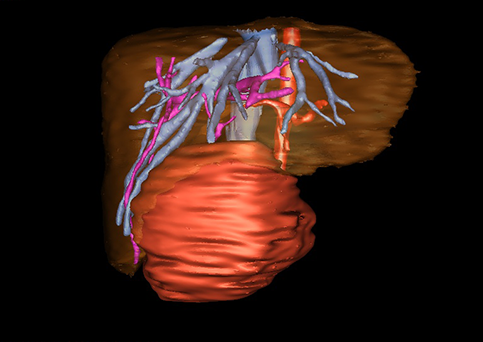

目前常用的检查方法有B超检查、CT、MRI、血管造影等。与其它的腹部肿块的诊断不同,对于小儿肝母细胞瘤血管造影具有重要的意义,可以作为手术前介入治疗的手段,也可为手术提供非常有效的影像学指导,但技术要求高,操作较复杂,且给患儿带来一定的痛苦。近年借助计算机辅助手术系统进行CT原始影像三维重建、手术规划和计算机虚拟手术技术,为精准肝脏手术提供了极为有效的技术支持。

近年来由于数字医学的发展,基于可视化三维重建技术的计算机辅助手术系统极大推进了小儿肝脏肿瘤的精准手术的进步。可以立体透视肝脏解剖、精确掌握肝段的边界、精确测算肝段乃至任意血管所支配的功能体积、准确定位病灶及其与邻近血管的解剖关系,最终对不同手术方案进行比较、筛选和优化。因此,计算机辅助手术规划系统是实现精准肝切除的有力辅助工具,是未来数字外科、精准外科等21世纪外科新理念的重要技术支撑。

计算机辅助手术规划系统具有良好的操作可行性、计算准确性和三维显示效果,可半透明、交互式显示真实的肝内立体解剖关系和空间管道变异,准确计算肝内管道的直径、走行角度,两点间的垂直距离,和任意血管的支配或引流范围等传统二维影像无法获取的信息,有助于实施个体化手术,提高了手术的确定性、预见性和可控性。计算机辅助手术规划系统可直观显示预留肝脏的结构和功能,并可通过虚拟切割功能辅助术者对手术方案进行蹄选和优化,系统评估手术风险和制定对策,改变了部分二维规划的术式和切除范围,使部分二维规划认为不能切除的患者成功手术,提高了手术的根治性、安全性和病变的可切除性,更加符合精准肝脏外科的术前规划要求。详见第11章。

随着计算机技术及影像检查技术的不断发展,以精确的术前影像学和功能评估、精细的手术操作为核心的精准肝切除技术日益受到重视。基于数字医学的计算机辅助手术技术(computer-assisted surgery,CAS)则是实现肝脏精准手术操作的基础。计算机辅助手术系统(CAS)可将术前二维(two dimensional,2D)的CT/MRI影像数据进行三维(three dimensional,3D)重建,建立个体化的肝脏三维解剖模型,清晰显示肝脏内脉管系统的走行及解剖关系,还原病灶与其周围脉管结构的立体解剖构象,准确地对病变进行定位、定性和评估,制定合理、定量的手术方案,实施个体化的肝脏血管取舍分配方案及实施精准肝脏手术。一般认为CAS包括:创建虚拟的患者的图像;患者图像的分析与深度处理;诊断、手术前规划、手术步骤的模拟;术中实时导航。应用本技术后,由于可以更清晰地看出肿瘤的界限,特别是根据肝血管的显影,判断出肿瘤与门静脉及肝静脉的关系以在手术前较准确地估计出手术成功切除的可行性。以往部分根据普通强化CT判断无法手术的病例而被评估为可以成功切除并手术成功。